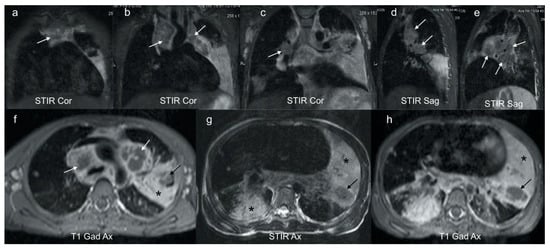

Figure 4. (ah): Coronal, sagittal and axial MRI in a 6-year-old girl with confirmed pulmonary TB. Coronal (ac) and sagittal STIR (d,e) images demonstrate characteristic low signal TB lymphadenopathy (white arrows) in the right and left paratracheal, and hilar regions. These can be compared with the higher signal axillary lymph nodes in image (c) which represent the appearance of non-TB nodes. Axial post gadolinium T1 at the level of the aortic arch (f) demonstrates that the STIR low signal lymphadenopathy in (ae) demonstrates rim enhancement (white arrows), typical of centrally necrotic TB nodes. In addition, there is homogenous enhancement of a dense left consolidation (star) with an area of non-enhancing low signal (black arrow), in keeping with parenchymal breakdown within the consolidation. The axial STIR (g) and corresponding gadolinium enhanced T1 (h) at the lower zone of the lungs demonstrates an intermediate-to-high STIR signal enhancing consolidation posteriorly on the right (star) in keeping with viable lung; an intermediate STIR signal, poorly and heterogeneously enhancing consolidation on the left (star) in keeping with at risk lung; and a T2 low STIR signal non-enhancing focal area on the left (black arrow) typical of TB necrosis (this is the opposite to the STIR signal of an abscess, which would be bright).

MRI is comparable to CT in the detection of lymph nodes >3 mm [22]. However, due to the lower spatial resolution, MRI is unable to detect small lymph nodes <3 mm. Normal lung parenchyma on MRI has a low signal and MRI is poorer at detecting subtle abnormalities such as ground glass opacification and mosaic attenuation [22]. MRI can, however, further differentiate TB lymphadenopathy from reactive lymph nodes based on signal intensity and heterogeneity. The presence of enhancement post contrast suggests active disease [2,3,21]. Short Tau inversion recovery (STIR)/T2-weighted MRI sequences may demonstrate characteristic low signal in TB lymphadenopathy and parenchymal necrosis [2] (Figure 4).

MRI is superior to CT in the characterization of tuberculous consolidation in that the MRI signal varies with the stage of necrosis and the presence of mycobacterium within the necrosis [2,23]. Caseous necrosis in TB consolidation demonstrates a characteristic low signal on T2-weighted sequences and is an indicator of active TB [2] [Figure 4].